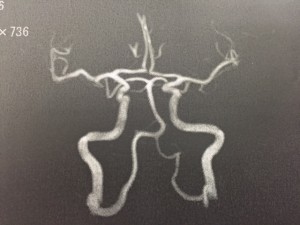

実は私、頭痛持ちなんです。最近の人は皆そうですよね。私は睡眠不足だし、不摂生で当然のことだと思います。私の場合は、閃輝暗点(せんきあんてん)といって眼がチカチカし始めると頭痛が酷くなるパターンです。昔からなので気にもしませんが、最近は本当に酷いです。なかなか病院に行く時間も取れず、ずっと我慢してましたが・・・限界。なんとか病院に行き検査をうけました。とても健康な脳でした。とても健康です。いつも通り偏頭痛という診断です。しっかり偏頭痛と向き合わないといけませんね。